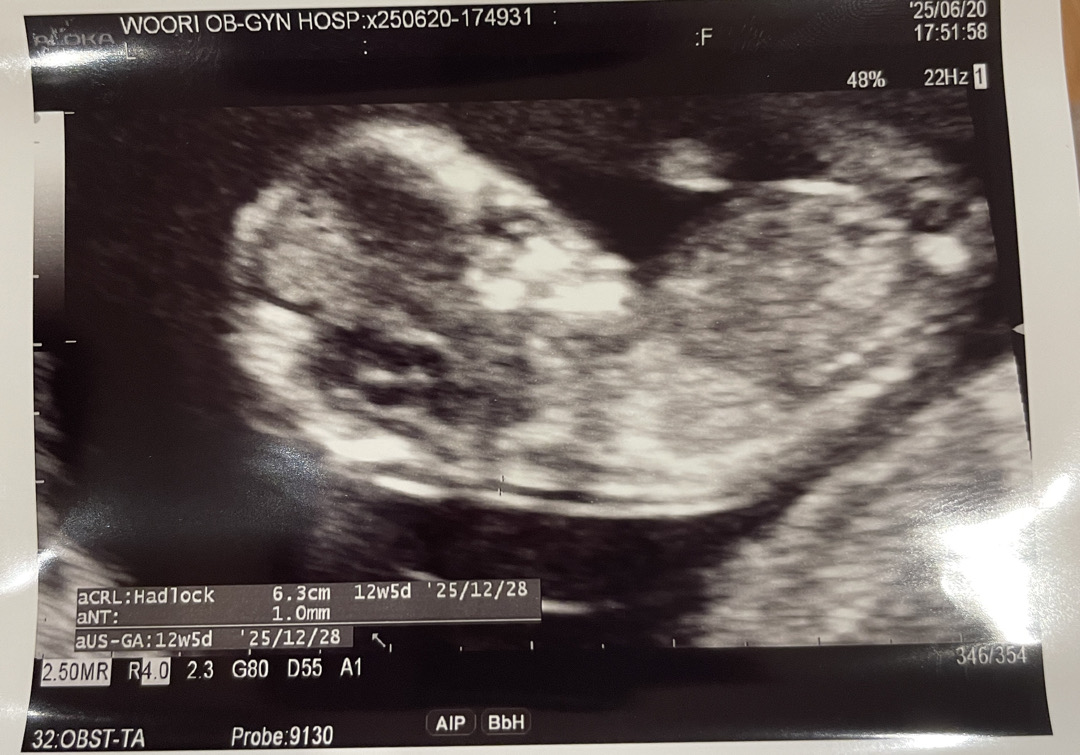

각도법 한번만 봐주세요!!

전 봐도봐도 모르겠네요 ㅠㅠ 봐주시면 감사하겠습니당!!